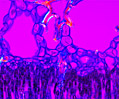

Lung Tissue